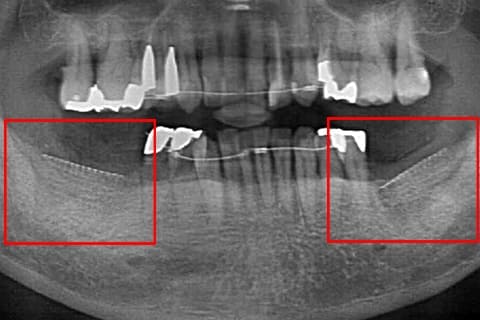

充分な骨の厚みと幅がインプラントを埋入するときに必要となります。しかし、歯を抜いた後に長期間経過すると歯を支えていた骨の吸収が進んでしまいます。同様に歯根の先が膿んでいる場合にも骨の吸収が進行します。

このようにGBR法は、十分な骨の厚みや幅がない場合や審美性を高くする場合に、骨の厚みや幅を増やす手法です。

骨移植であるボーングラフトは、歯槽骨が吸収され骨幅が薄くなりインプラントが埋入できない症例で行う手法です。

この方法は十分な量の骨が得られない場合に、自身の骨を必要最小限ブロックで切り出し、骨が薄く足りなくなった箇所に移植することで必要な骨を作り出します。